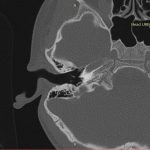

- Diagnosticul traumatismelor de bază de craniu

- Diagnosticul fracturilor:

-

- Unice

- Multiple

- Cu înfundare

- Complexe cranio-sinusale

- Complexe cranio-etmoidale

- Complexe cranio-orbitare

- Complexe cranio-faciale